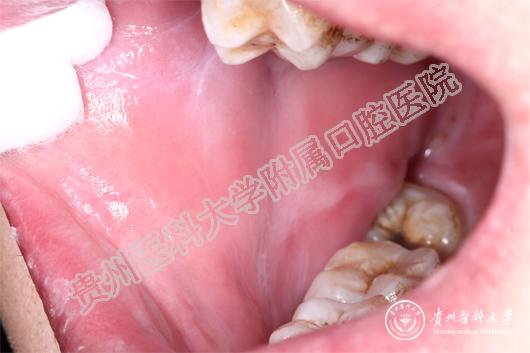

(患者治疗前后的口腔黏膜病损对比 上图:治疗前,下图:治疗1周后)

当天值班的王珣主治医师为小邓这一特殊病人加号,并作了相关检查后诊断小邓为药物引起的“过敏性口炎”。王珣介绍:小邓来的时候已经很严重了,上下唇、手背、拇指已经出现红色斑块,并且全口黏膜溃烂、生殖器可见不规则糜烂面。像小邓这种情况根本无法进食、而且疼痛难忍。若不及时救治,很有可能造成电解质紊乱。随后王珣医生询问病史发现:原来,5天前,小邓因智齿冠周炎自行服用了“消炎片”,随后出现全口黏膜溃烂,无法进食而且说话都困难,随后皮肤上也起红斑,生殖器也开始溃烂,疼痛难耐,无法入睡,人也明显消瘦了许多。

王珣叮嘱患者停用可疑药物,并为他对症用药。由于“过敏性口炎”的病情发展变化较大,王珣医生还为患者留了自己的微信,以便实时了解小邓的病情变化。1周后,小邓复诊时口腔生殖器黏膜已经痊愈,上下唇及手背、拇指的斑块也基本消退。小邓非常感谢awc777万象城娱乐官网附属口腔医院,在疫情的特殊时期能为他开通绿色通道,让他的疾病痊愈 。